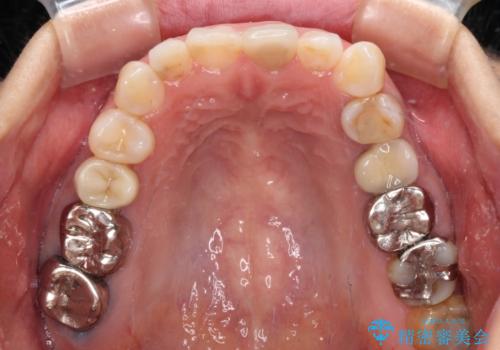

当院では治療前の歯列が整っていない限り、下顎前歯の舌側をワイヤーで固定するようにしています。下顎のみの部分矯正としたことで、マウスピース保定の負担を軽減することができました。

上顎は、失活して歯の色が変色しているため、将来的に補綴治療で自然な口元に仕上げていきたいとのことでした。